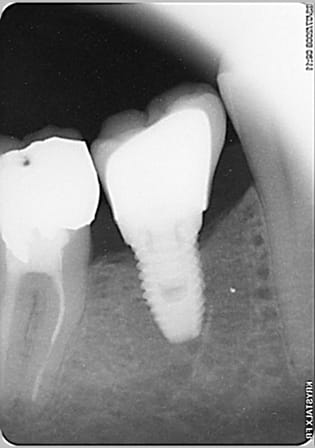

voila l'implant dont je parlais. Trop court, pas dans l'axe... pas content le manu.

L'implant est un nobel speedy à hexagone externe, que je ne recommande à personne (chiant a poser, chiant pour l'empreinte)

sur le scan un implant de 9 mm était trop proche du nerf dentaire, alors que de toute évidence j'avais la place puisque celui la est un 8,5.

apres l'axe de l'implant est tres lingualisé ce qui peut expliquer que sur la rétroalveolaire on se retrouve loin du fond de l'alveole d'extraction.

Quelques nouvelles de cet implant dans cet os dense:

J'ai fait le controle à 1 mois samedi et tout va bien, pas de douleur,pas de mobilité, petite apparition de la vis de cicat en lingual, OUF!

La radio c' est ok et son angulation est finalement beaucoup moins distale que sur la radio de pose car l'angulateur n'a pas bougé.